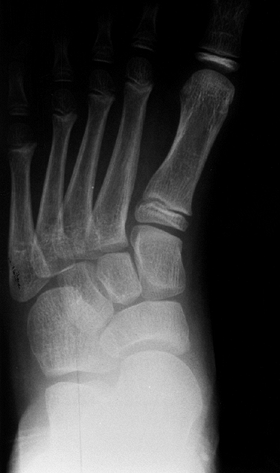

both clinically and radiographically in order to define healthy and

pathologic states. Radiographically, images are always taken in the

standing position, except in the case of infants, for whom position

should be specified. In standing anteroposterior and lateral views of

the foot, the following angles should be determined (Fig. 30.3):

-

The lateral talocalcaneal angle (A)

(lateral view) is measured as the angle subtended by the long axis of

the talus and the plantar surface of the calcaneus. Normally, it is in

the 30 to 45-degree range. It is decreased in the varus foot and

increased in the valgus foot (Fig. 30.3B). -

The anterior talocalcaneal angle (B)

(anteroposterior view) is measured as the angle subtended by the long

axis of the talus and the long axis of the calcaneus. Normally, it is

30 to 45 degrees, decreased in a varus foot and increased in a valgus

hindfoot (Fig. 30.3A). -

Meary angle (lateral view) is the

measurement of the angle subtended by the long axis of the talus and

the long axis of the first metatarsal on a standing lateral view.

Normally, these lines are colinear. In cases where the apex is directed

dorsally, a cavus foot is present. Cases where apex is angled

plantarward are valgus or flatfeet (Fig. 30.3B). -

Intermetatarsal angle (C)

(anteroposterior view) is the measurement of the angle subtended by the

long axis of the first and second metatarsal. This angle is generally

less than 5 degrees but is increased in deformities associated with

bunion formation (Fig. 30.3A). -

The longitudinal arch (D) (Hibb angle,

lateral view) is generally measured as an angle between the plantar

surface of the calcaneus and the first metatarsal. It is decreased in

cavus feet, particularly with a “calcaneus” deformity in which the

longitudinal axis of the calcaneus is increasingly vertical (Fig. 30.3B). -

Calcaneal pitch (E) (lateral view) is

measured as the angle between the horizontal and the plantar surface of

the calcaneus. It is an indicator of the position of the calcaneus in

stance and is particularly important in evaluating a cavus foot or

clubfoot (Fig. 30.3B).

![]() |

Figure 30.3 The standard radiographs of the foot are taken in the standing position, anteroposterior and lateral views. A: On the anteroposterior view (A), the intermetatarsal angle (C) between the first and second metatarsal and the talocalcaneal angle (B) can be measured. B: On the lateral view of the foot, the lateral talocalcaneal angle, the Meary angle, the Hibb angle (D), and the calcaneal pitch (E) should be determined.